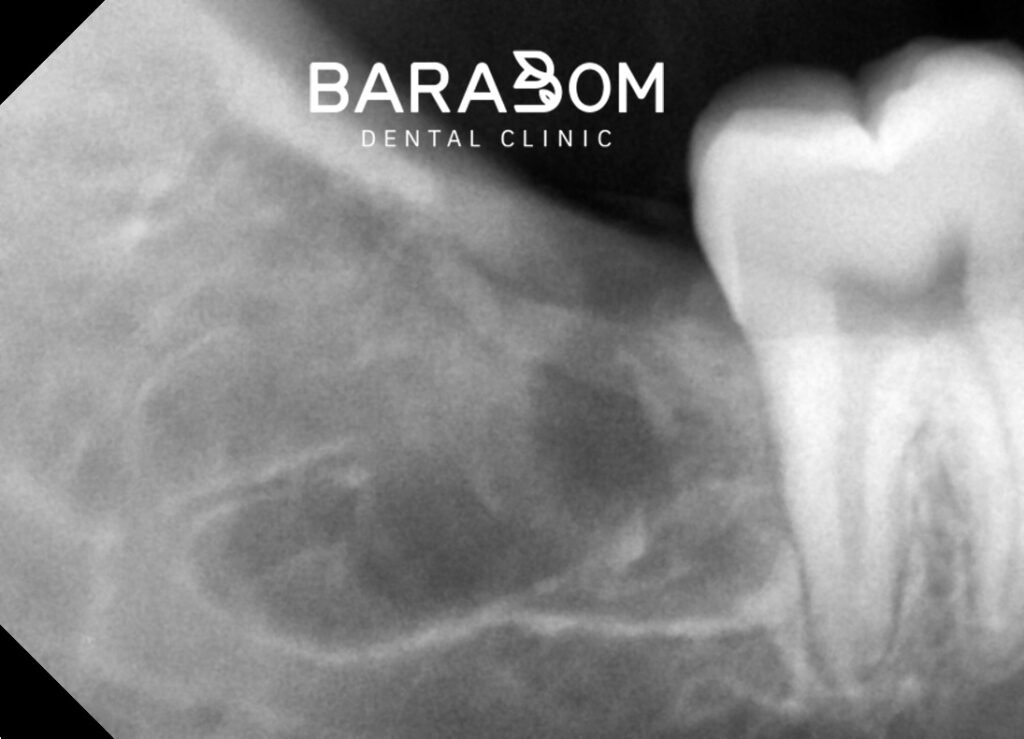

이번엔 엑스레이를 확인해 보겠습니다.

신경관과 치아 사이 위치가

가까운 것을 확인할 수 있습니다.

다만, 파노라마 촬영만으로는

사랑니와 신경관의 정확한 위치 관계를

파악하기 어렵습니다.

3D-CT 촬영을 통해 신경관의 위치를

입체적으로 분석하는 과정이 필요하죠.

CT 판독 시 확인하는 내용은

신경관과 치근의 거리,

신경관의 주행 방향,

치아 분할 시 안전 영역 등입니다.

따라서, 3D-CT를 이용하여

각 부위별로 신경관과의 위치와

치근의 거리를 체크하여

진료 계획을 수립해야 됩니다.

하치조신경이 치아 하방 3mm 지점에 위치한다면

치아를 분할할 때 절삭 기구가

그 이상 내려가지 않도록 계획을 세웁니다.